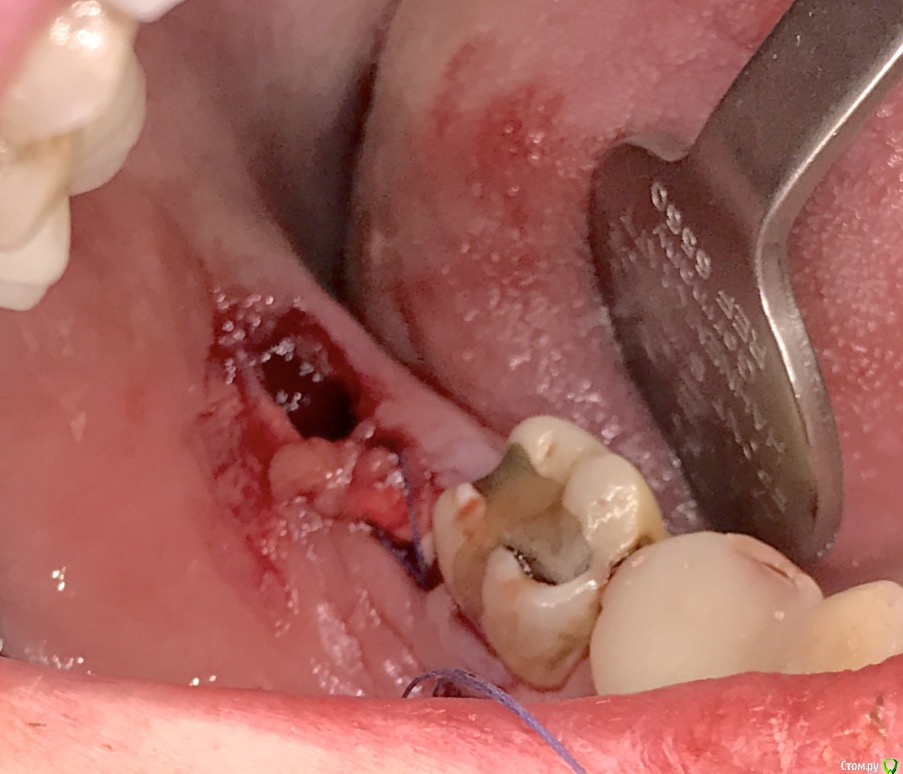

колесников Опубликовано 19 марта, 2017 Поделиться Опубликовано 19 марта, 2017 Здравствуйте коллеги! Есть несколько проблем которые мне не давали покоя своей неразрешимостью. Одна из них это постэкстракционное ведение лунки нижних восьмых. Со временем пришёл к протоколу который начал устраивать меня и пациентов. Но вылезла проблема которую никак не удавалось решить: щелевидный дефект в лоскуте у дистального корня 2го моляра. Герметизма не удавалось достичь,вторичное инфицирование со всеми вытекающими. Пробовал разные виды лоскута,швов,прф,но без особого успеха. Особенно часто такая проблема возникает при горизонтальном положении 3го моляра с редуцированной межзубной перегородкой. Наконец проблема решена. К обычному протоколу я добавил расщеплённый ротированый лоскут на питательной ножке. В результате лоскут дистально у шейки 2го моляра получается двуслойным и независимым. Если края верхнего слоя по тем или иным причинам разойдутся, у нас есть второй,по которому как по рельсам вторично наползет эпителий. Ссылка на комментарий

колесников Опубликовано 20 марта, 2017 Автор Поделиться Опубликовано 20 марта, 2017 Вы правы,сгусток не держится. Потому стараюсь от него избавиться,заполняю лунку графтом. Под турундой не могу себе позволить вести лунку,мне нужно минимизировать посещения ,максимум два,а лучше одно. Насчёт риска:все по ситуации,зависит от положения зуба,когда язычно лоскут истончен,всегда можно в ретромолярном пространстве поискать. Есть ещё вариант, потом как нибудь пост сделаю по консервации лунки после имплантации. 1 Ссылка на комментарий

колесников Опубликовано 21 марта, 2017 Автор Поделиться Опубликовано 21 марта, 2017 Нет сгустка-нет проблем связанных с его распадом. Конечно и графт может инфицироваться.для этого и нужен полный герметизм. Внутренний лоскут пришивается как сст. Снаружи (вестибулярно ,примерно на середине 7ки)заводится игла,подхватывается лоскут и выводится снова наружу, Натянули,зафиксировали. Расщеплять там где толсто,понятно,что не всегда это язычно. Есть ещё вариант : выделить фрагмент ретромолярно и после вести разрез по язычной кромке. Получается такая длинющая змейка,которую можно хоть в рулон свернуть. 1 Ссылка на комментарий

колесников Опубликовано 23 марта, 2017 Автор Поделиться Опубликовано 23 марта, 2017 Ушивание ран нижних 8-ых бесполезная процедура. герметичности все одно не добьетесь а риск абсцедированния возрастает+швы в подвижной зоне. 1-в моем графике нет лишнего времени на бесконечные перевязки,звонки от пациентов и прочую нервотрепку,мне нужен контроль и прогноз заживления,потому ушивание лунки 8ок для меня необходимая вещь. 2-пост именно об одном из способов герметичного ушивания лунки. 3- почему риск абсцедирования должен вырости если у меня нет вторичного инфицирования из-за герметичности и нет первичного т.к. нет сгустка и его распада ,плюс атравматичное удаление и комбинированная антибактерапия? 3-дизайн разреза и соответствующие швы позволят вам не опасаться подвижной зоны, Ссылка на комментарий